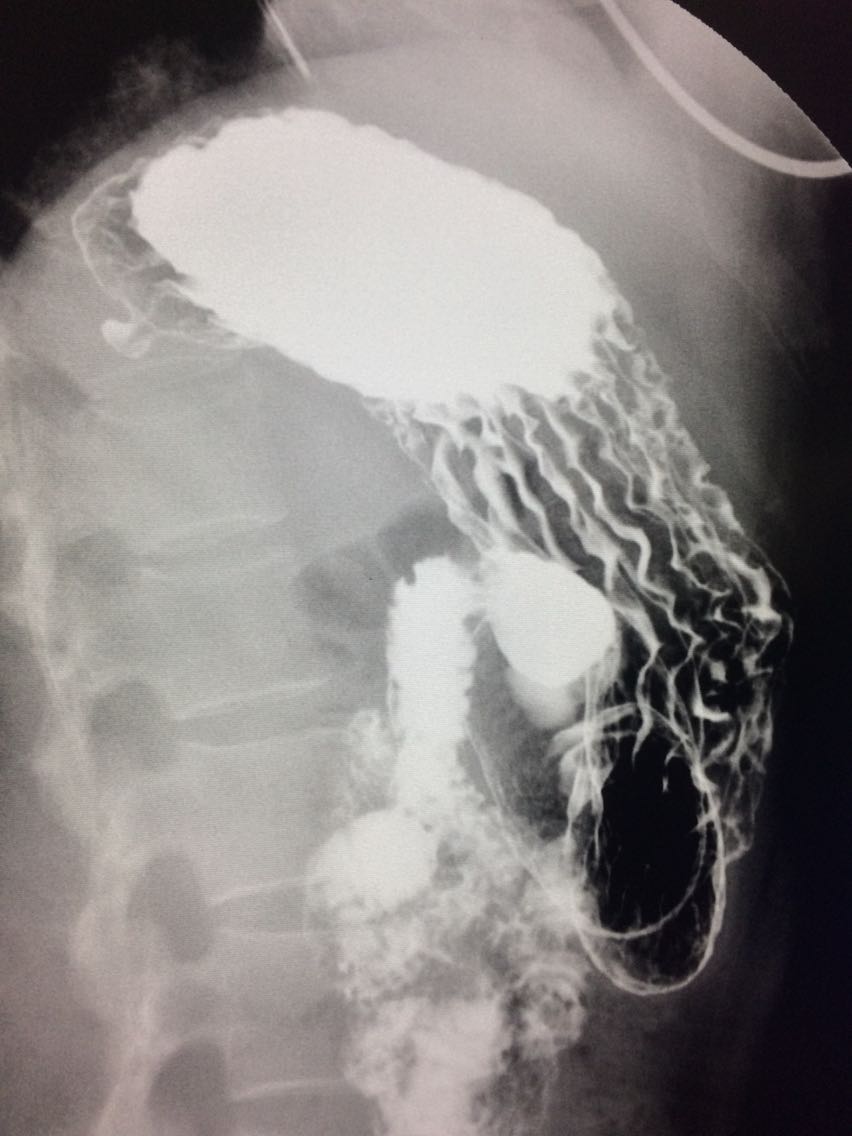

胃底憩室一例

女.47岁 体检来诊。 平素体健,无明显症状。 做上消化道造影如图。

诊断,胃底憩室。 治疗,患者无明显症状,未予治疗。